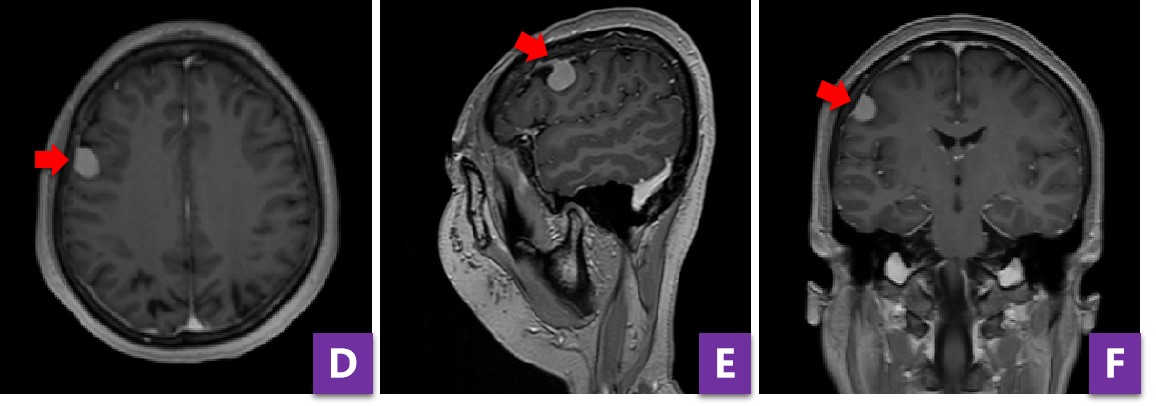

图6 开颅后4小时复查头CT,提示肿瘤切除彻底,无出血,骨瓣复位良好

脑膜瘤是最常见的颅内原发肿瘤之一,目前治疗首选手术切除,术中需要把肿瘤连同周边受累硬膜一并切除,若有颅骨受侵也要同时处理,这样才能做到肿瘤的根治。当然具体手术的风险、并发症和住院时间等,还要根据每一个病人的具体情况进行判断。